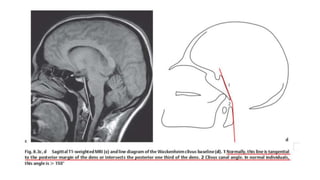

McGregor’s line (basal line)

Line drawn from posterior tip of

Hard palate to lowest part of

Occiput